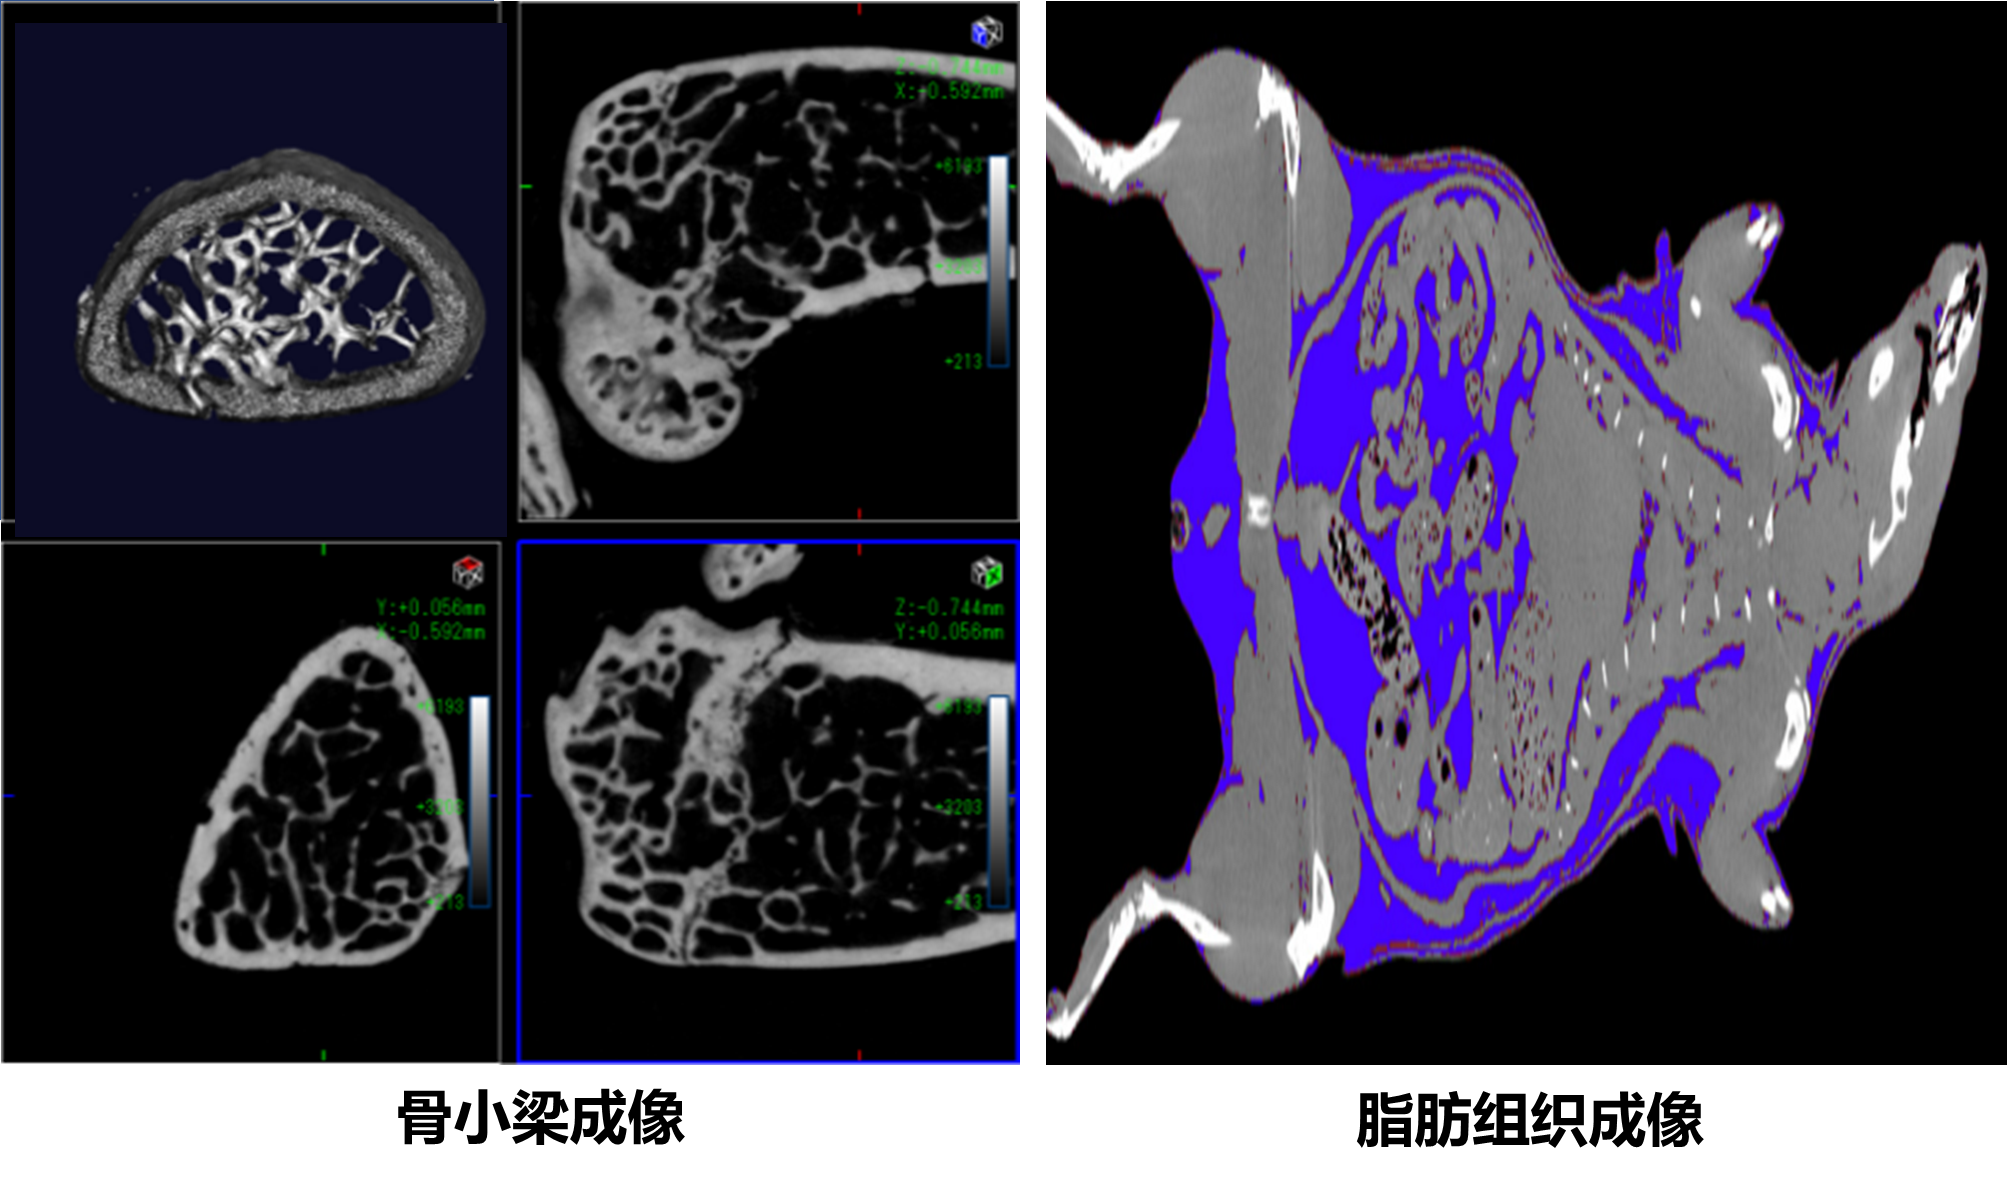

经维修后检测,设备整体状态良好,CT仪器拍摄在最高分辨模式下分辨率约达10lp/mm,最高拍摄速度约达60帧/秒(4x4 binning),14位数字输出,通讯协议与现有设备通信协议保持一致,数据可以无缝对接,灵敏度达到5mGy。此外,通过反复比对并优化拍摄电压等参数,在确保图像采集质量不下降的前提下,显著降低了设备损耗,从而有效延长了其使用寿命。

该设备支撑高等医学研究院、基础医学院、口腔学院、齐鲁医院等学院及附属医院在口腔、骨骼、心血管、肿瘤等方面高效开展科学研究;助力“胃肠道间质瘤治疗的脂肪酸和类固醇膜受体的靶点发现、功能研究及靶向药物的发展”等多项国家自然科学基金项目落地;支撑十余篇科研文章在《Science Advances》、《Cell Death &Disease》、《Molecular Pharmaceutics》等高水平学术期刊上发表。